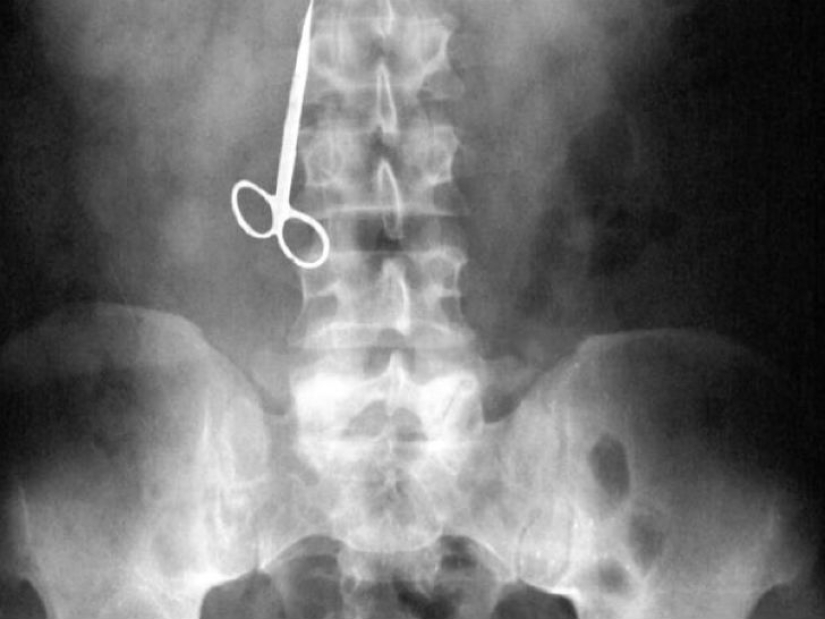

One woman did not find toothpicks at home after lunch and decided to use scissors.